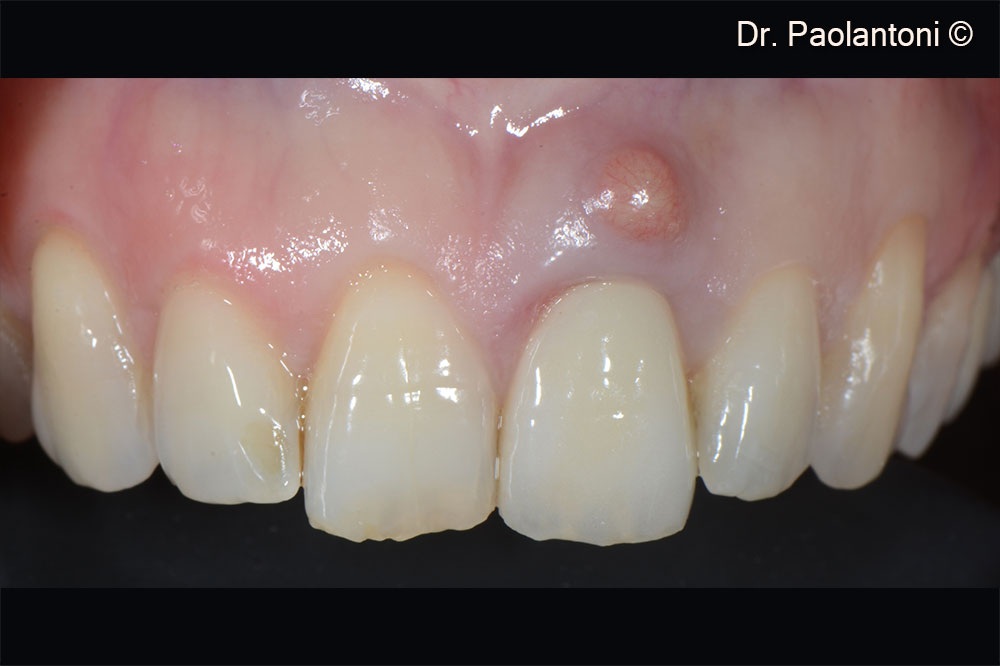

Aspect of the edentulous area after six months

Close-up view of the peri-implant tissue